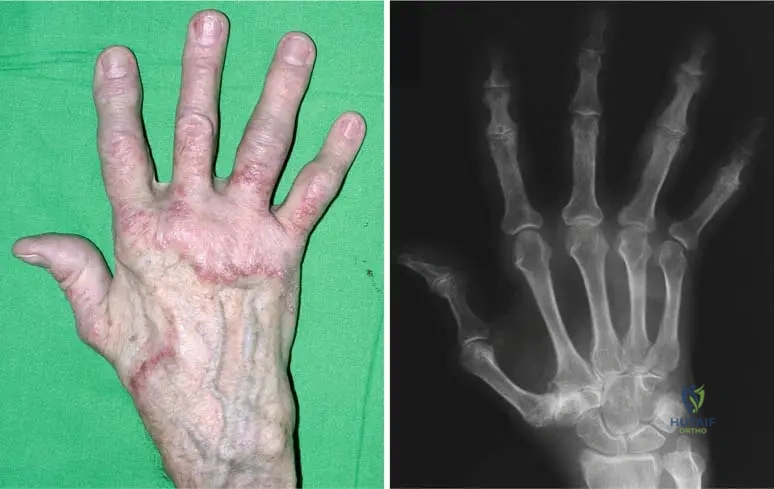

A 4-year-old boy is brought to the clinic due to concerns about his skin. His parents describe his skin as being unusually stretchy and delicate. Physical examination confirms significant skin hyperelasticity, particularly noticeable in his lower extremity and neck region, as depicted in the provided images. This finding is a characteristic manifestation of which condition?

Rationale: The vignette describes a 4-year-old boy with significant skin hyperelasticity, especially in the lower extremity and neck, which is directly illustrated by the provided images and described in the text as "Fig. 12.7 a, b Skin hyperelasticity of a 4-year-old boy in lower extremity (a) and in the neck region (b)". The text identifies this as a characteristic of Ehlers-Danlos Syndrome. Marfan Syndrome primarily affects the cardiovascular, ocular, and skeletal systems, while Osteogenesis Imperfecta involves bone fragility. Neurofibromatosis Type 1 is characterized by café-au-lait spots and neurofibromas, and Epidermolysis Bullosa by extreme skin fragility leading to blistering, none of which match the described skin hyperelasticity.

A 4-year-old boy is being evaluated for generalized joint hypermobility and skin hyperelasticity, as depicted in the clinical images. His parents also report that he bruises very easily. These findings are characteristic of Ehlers-Danlos Syndrome. Which of the following is NOT listed as an extraskeletal manifestation of this syndrome in the provided text?

Rationale: The vignette describes a child with classic features of Ehlers-Danlos Syndrome, consistent with the provided images. The question asks which option is NOT an extraskeletal manifestation listed in the text. The text explicitly lists "respiratory and cardiac complications due to pulmonary hypertension, heart dilatation, and particular aortic dissection" and "Neurologic complications are sensorineural deafness, chorea and cerebellar ataxia, and percussion myotonia." Renal cysts are not mentioned anywhere in the provided text as an extraskeletal manifestation of Ehlers-Danlos Syndrome.